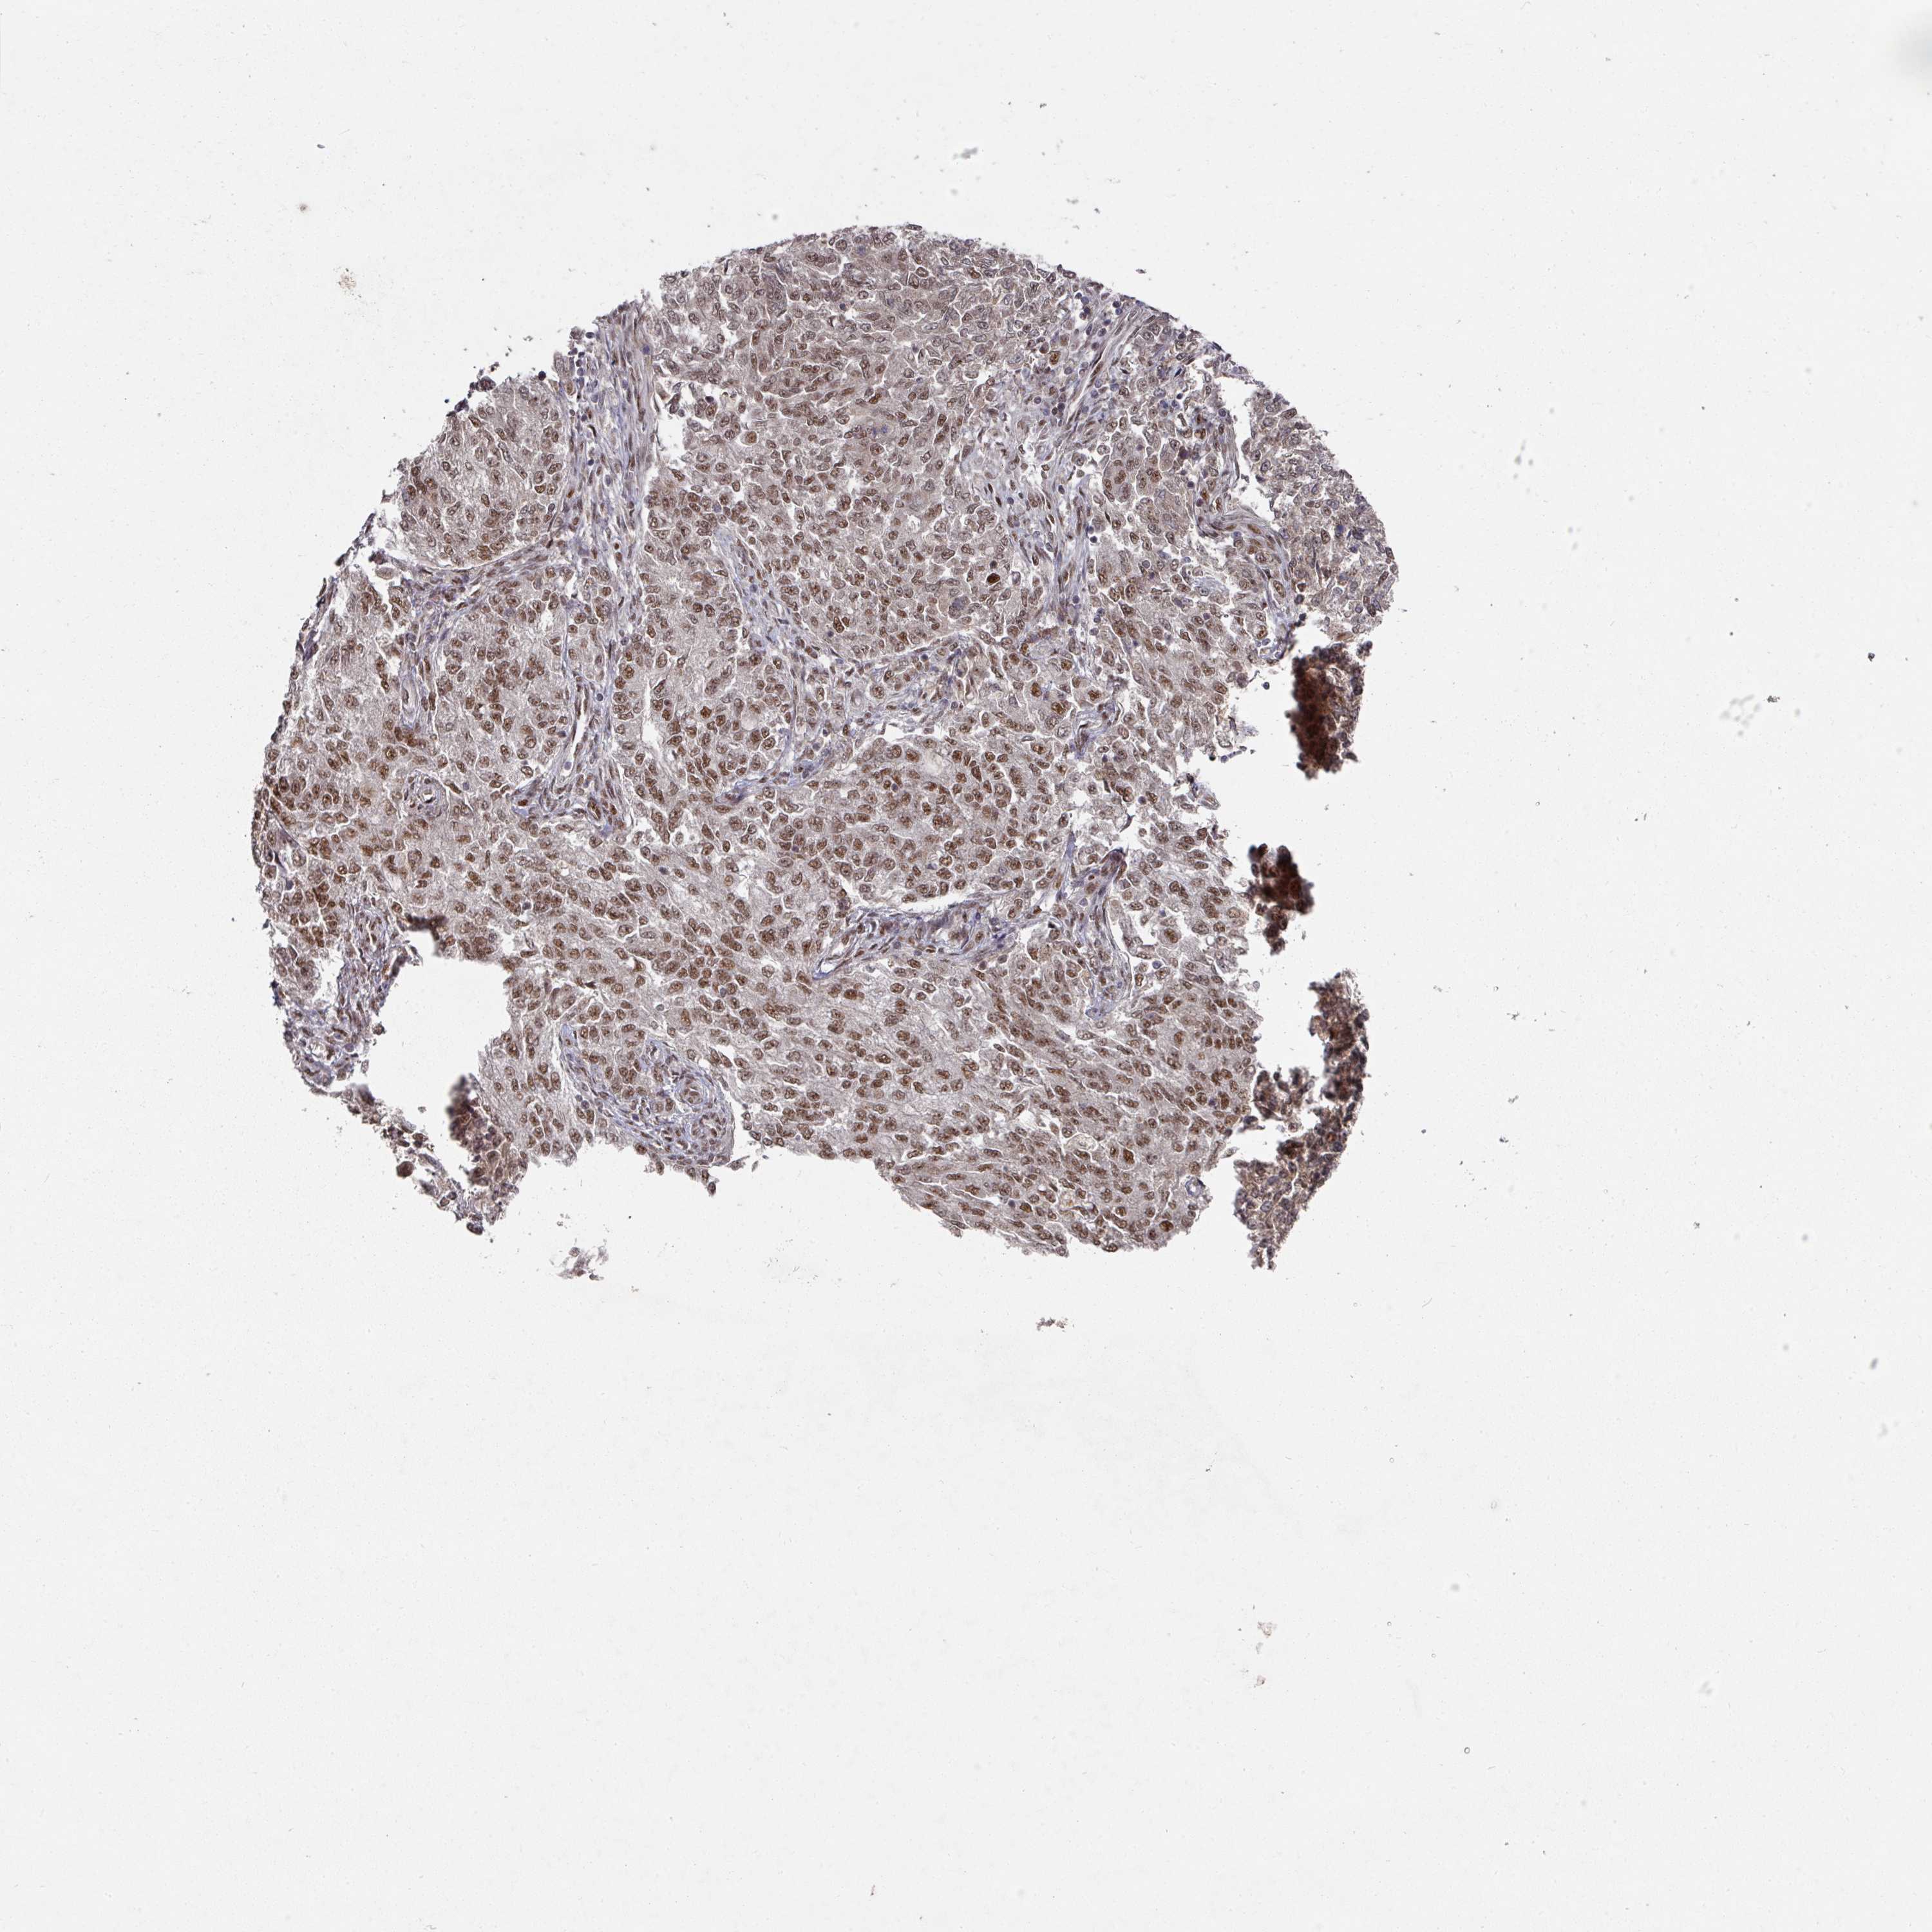

ENDOMETRIAL CANCER - Protein expressioni

A mouse-over function shows sample information and annotation data. Click on an image to view it in a full screen mode. Samples can be filtered based on level of antibody staining by selecting one or several of the following categories: high, medium, low and not detected. The assay and annotation is described here.

Note that samples used for immunohistochemistry by the Human Protein Atlas do not correspond to samples in the TCGA dataset.

Antibody stainingi

Antibody staining in the annotated cell types in the current human tissue is reported as not detected, low, medium, or high, based on conventional immunohistochemistry profiling in selected tissues. This score is based on the combination of the staining intensity and fraction of stained cells.

Each image is clickable and will lead to virtual microscopy that enables deeper exploration of all samples and also displays staining intensity scores, fraction scores and subcellular localization as well as patient and tissue information for each sample.

Antibody HPA051587

Antibody CAB026384

Staining

High

Medium

Low

Not detected

Intensity

Strong

Moderate

Weak

Negative

Quantity

>75%

75%-25%

<25%

None

Location

Nuclear

Cytoplasmic/membranous

Cytoplasmic/membranous,nuclear

Carcinoma, NOS